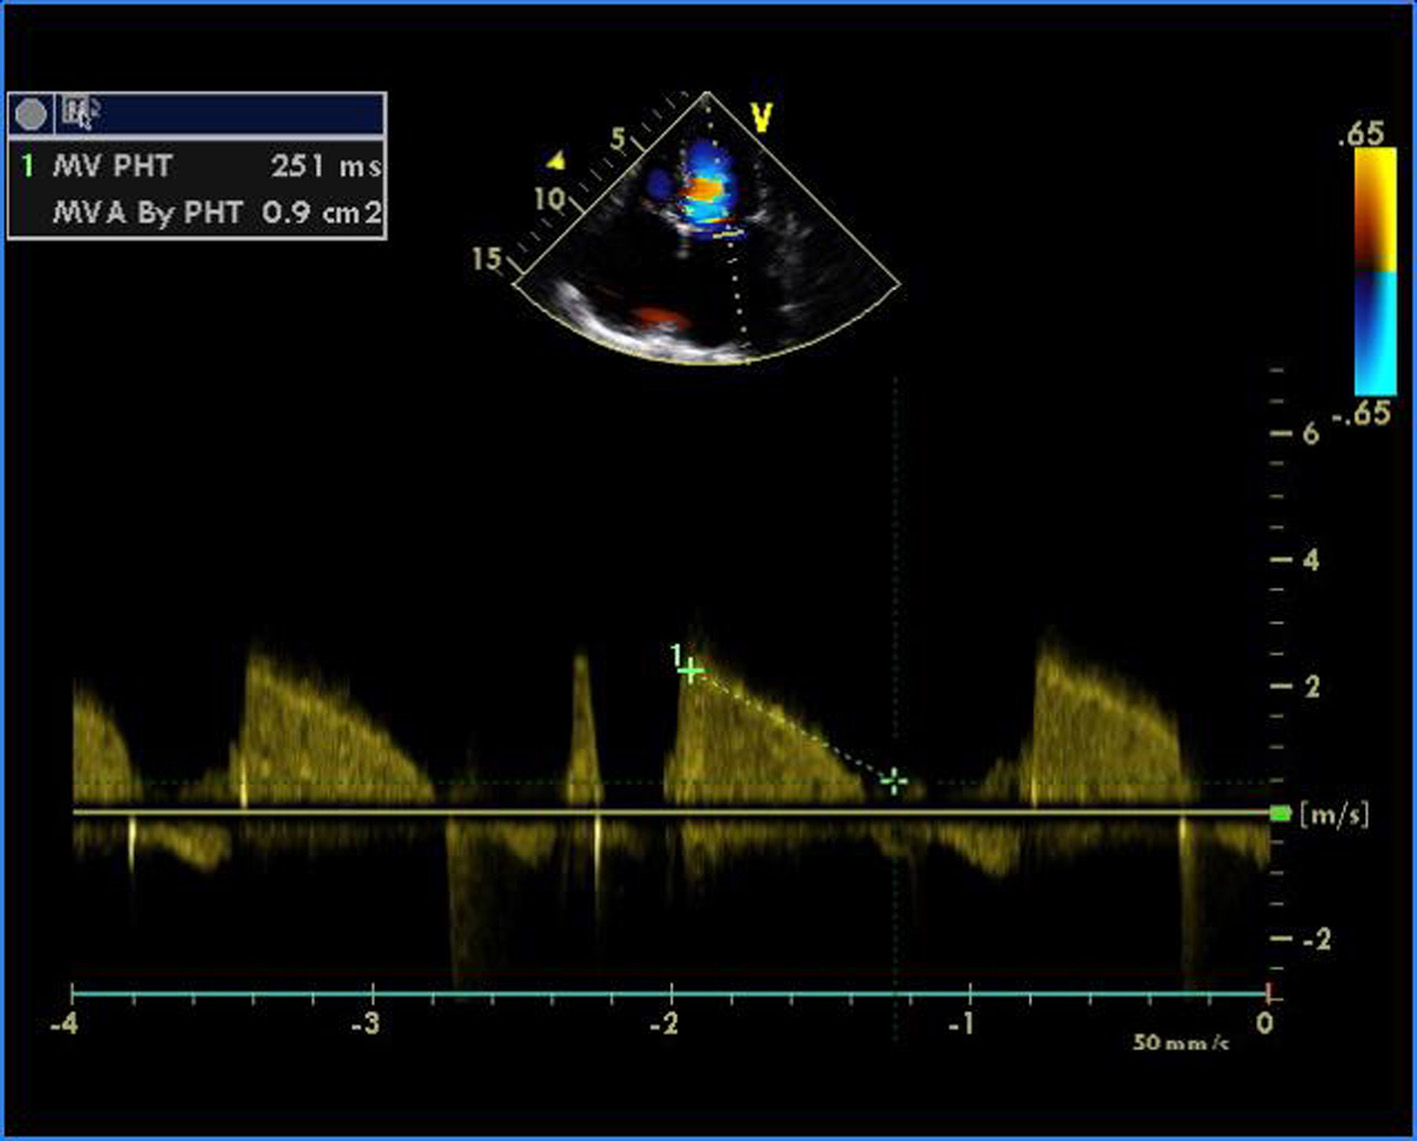

Figure 1. Transthoracic echocardiogram of apical four-chamber view showing thickened and doming mitral valve and tricuspid valve.